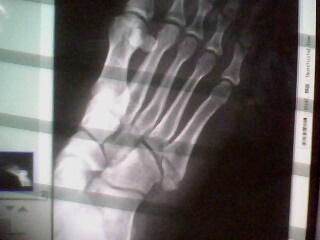

(紅色圈起處 為斷骨處)

一照X光 果然 證實喵族的猜測

右腳"趾骨"斷裂 現在回想起來

也就是 我在扭到的時候 活活掰斷了自己的骨頭